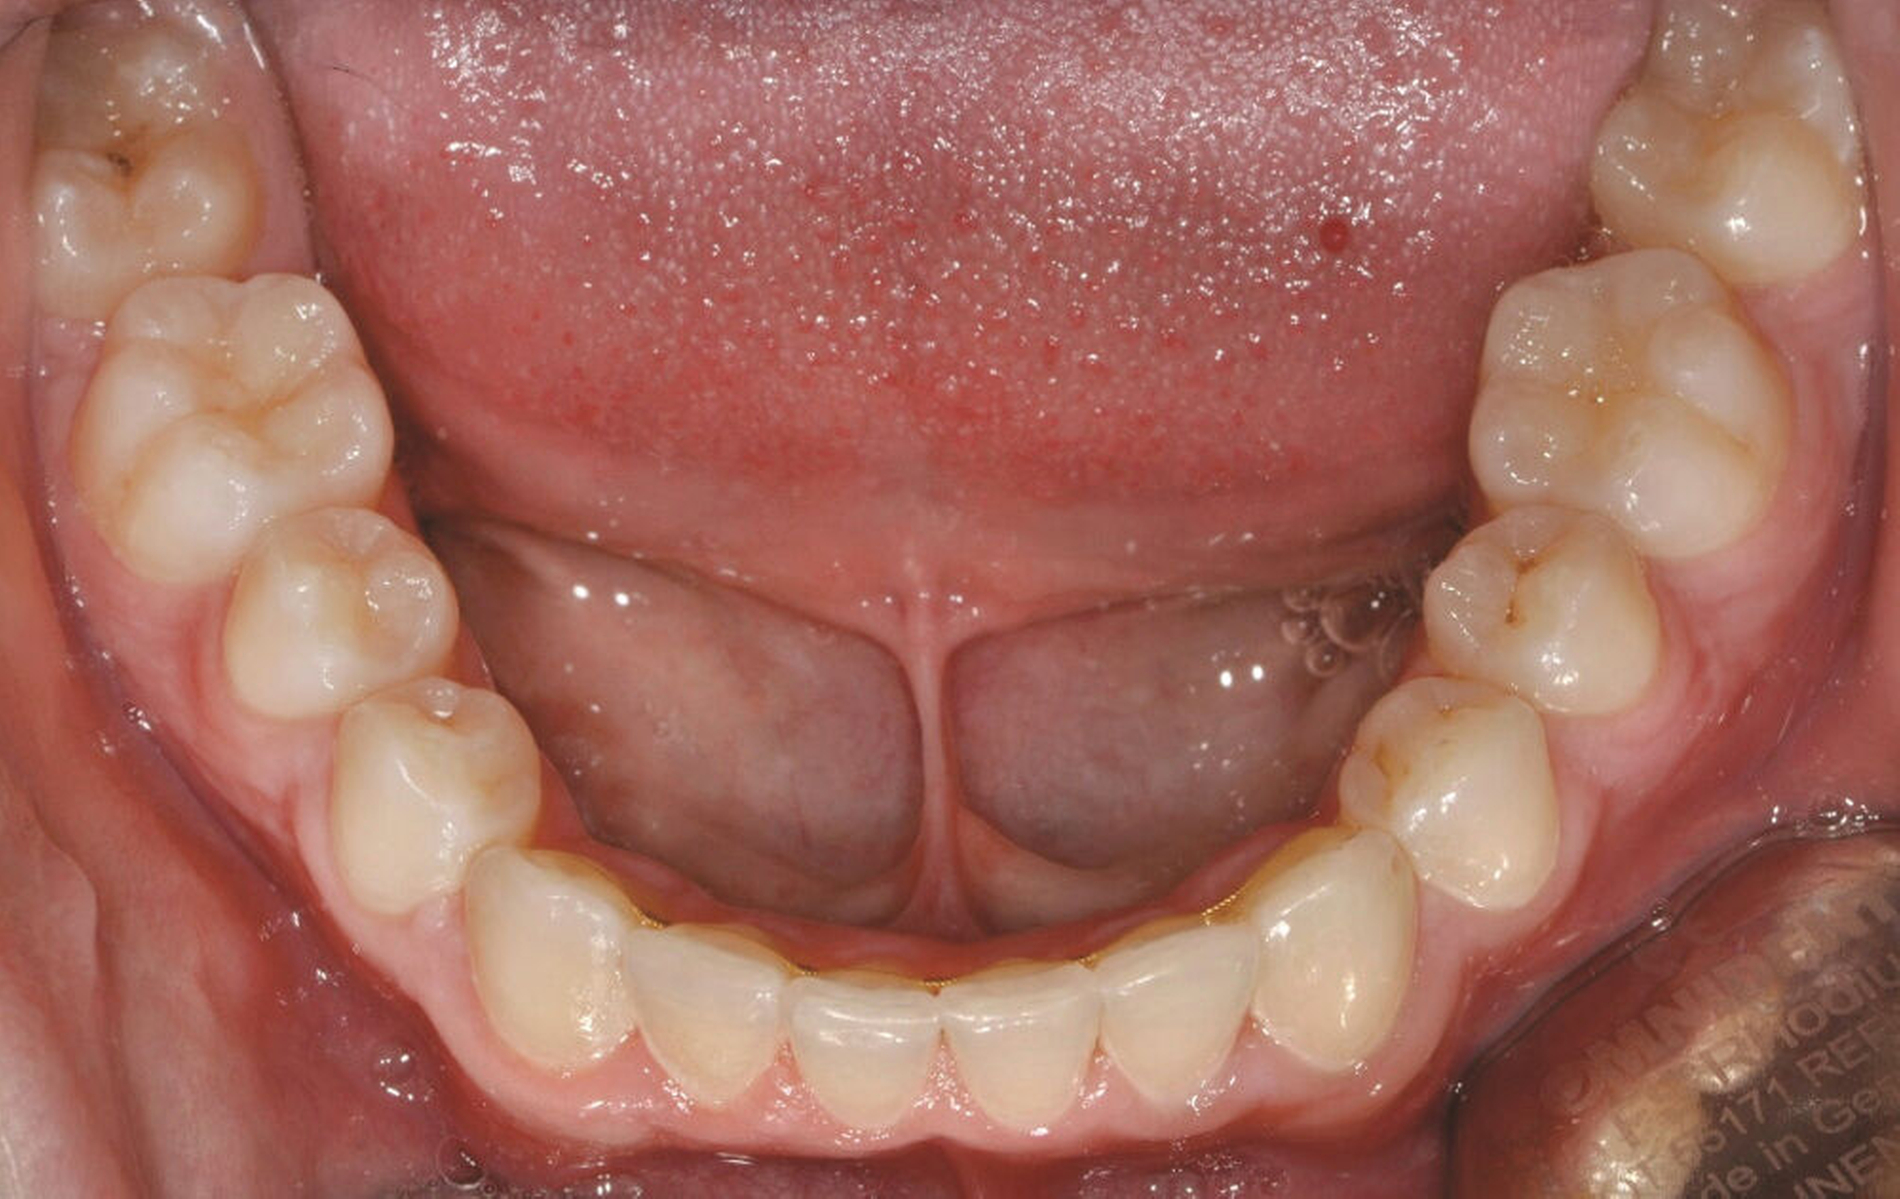

Bei der Erstvorstellung zeigt der Patient ein ausgeprägtes Diastema mediale sowie Restlücken und Asymmetrien im Oberkieferfrontzahnbereich nach kieferorthopädischer Therapie alio loco (Abbildung 1). Aufgrund mangelnder Adhärenz konnten nicht alle kieferorthopädischen Behandlungsziele erreicht werden, was insbesondere aus ästhetischer Sicht Herausforderungen für den restaurativen Lückenschluss mit sich bringt. Erschwerende Faktoren sind die Verschiebung der Mittellinie, die Achsenneigung der Zähne 13, 12, 22 und 23 sowie die inhomogene Lückenverteilung mit ungleich verteilten Lückengrößen (Abbildung 2). Eine erneute kieferorthopädische Korrektur lehnt der Patient allerdings ab. Subjektiv empfindet er insbesondere das kindliche Erscheinungsbild der lückig stehenden, kurz und klein wirkenden seitlichen Schneidezähne als störend. Ziele der Behandlung sind eine präventionsorientierte, ästhetisch-funktionale Rehabilitation des Oberkieferfrontzahnbereichs und eine Harmonisierung des dentofazialen Erscheinungsbildes.